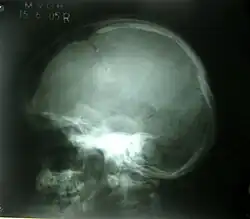

A common disease associated with the crown includes the cerebrospinal fluid leak, which involves the excess removal of fluid within the meninges. The cerebrospinal fluid leak is mainly caused by a head, brain, or spinal injury which tears the meninges membrane. The excessive leakage of the cerebrospinal fluid leads to symptoms that include intense headaches often localised to the crown.[13] An extreme sign of this disorder includes the leakage of fluid from the patient's ears and nose.[13] The diagnosis of the cerebrospinal fluid leak is determined from examinations including a computerised tomography scan which involves an X-ray image of parts of the skull including the crown.[14] Health professionals offer treatments to manage the symptoms associated with the disease. For example, consuming fluids such as water aims to stop excess leakage and reduce headaches, and antibiotics are also provided if signs of infection are clear such as fever and chills.[15]

Bone fractures to the crown of the head are linear or depressed and range in severity based on the impact to the skull. The linear fracture involves a break to the skull whereas the depressed fracture results in the scatter of skull fragments.[19] The skull fractures are mainly caused by incidents involving a vehicle, assault, or a fall. In more severe cases, penetrating skull fractures are caused by an object such as a metal rod or bullet breaking through the skull completely. Based on the severity of the fracture, symptoms may include nausea, memory loss, concussion, bruise, and lethargy. Another symptom such as bleeding results in the build-up of pressure in the skull since it is an enclosed cavity and thus pushes the brain to the brainstem opening leading to a coma.[20] Diagnosis occurs due to a range of physical exams which identifies the extent of the injury and possible treatments. For example, the computerised tomography scan identifies the site of the fracture and any associated injuries to the brain, whereas magnetic resonance imaging highlights the damaged tissue. The treatments of severe skull fractures include surgery and medication to avoid infection, however, for linear fractures treatment involves rest for approximately 5 to 10 days, so that the crown can heal.[21]